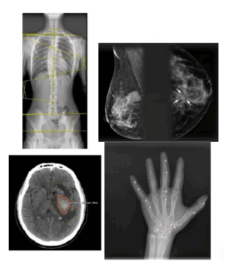

- Imaging modality, e.g. CT, MRI, X-ray, Angio etc.

- Use conditions: e.g. lesion detection, scoliosis analysis, bone age assessment, fractures, pneumonia, PE, ICH, etc.